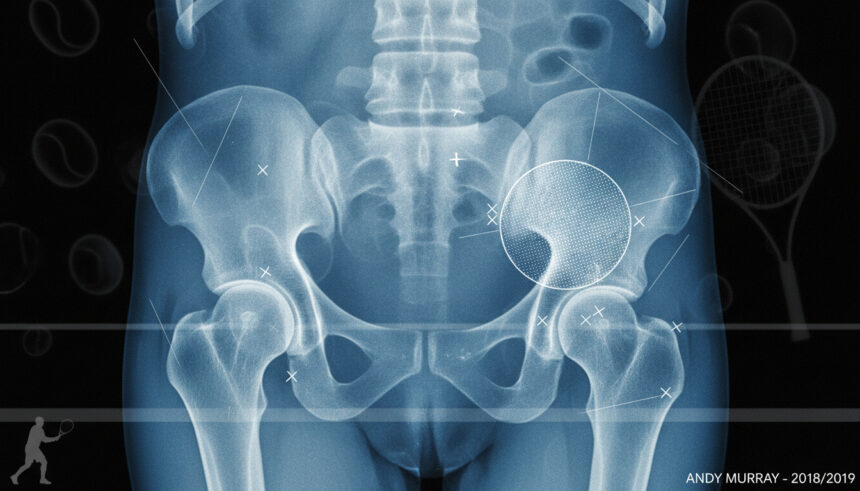

Andy Murray’s hip resurfacing surgery and the corresponding andy murray xray image became flashpoints in tennis and medical news. On January 28, 2019, in a London hospital, Murray underwent a Birmingham Hip Resurfacing procedure on his right hip with a metal-on-metal implant – a fact confirmed by the official xray shared on Instagram. The update dispels online rumors by providing verified facts, direct quotes, and clear timelines.

Xray Evidence Official xray image shared by Murray shows metal hip implant

“I underwent a hip resurfacing surgery in London yesterday morning…feeling a bit battered and bruised just now but hopefully that will be the end of my hip pain. I now have a metal hip as you can see in the 2nd photo.”

Andy Murray, via Instagram (Hello Magazine)

The andy murray xray released in early 2019 confirmed a successful Birmingham Hip Resurfacing surgery, verified by direct sources and an official xray. This update dispels rumors and provides clarity on his procedure, current recovery, and future medical monitoring.

A: The xray Murray shared shows a metal Birmingham Hip Resurfacing (BHR) implant in his right hip, confirming surgery success and hardware position (MatOrtho).